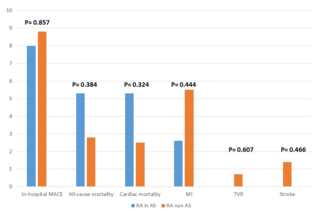

FFR(X)pred was compared with FFR(X)true. A close correlation (r2 = 0.92) was found between FFR(X)pred and FFR(X)true (Figure 4A). The corresponding Bland-Altman plot shows a small overestimation (Figure 4B). FFR(X)app was also compared with FFR(X)true (Figure 4C). Although a moderate correlation (r2 = 0.60) was found, a relatively large scatter was observed in the plot of the relationship between FFR(X)app and FFR(X)true. The corresponding Bland-Altman plot shows that FFR(X)app systematically overestimates FFR(X)true (Figure 4D). The difference between FFR(X)app and FFR(X)true was significantly higher compared with the difference between FFR(X)pred and FFR(X)true (0.18 ± 0.10 vs 0.05 ± 0.05; P<.001 in paired t-test).

FFR(X)app and FFR(X)true. The corresponding Bland-Altman plot shows that FFR(X)app systematically overestimates FFR(X)true (Figure 4D). The difference between FFR(X)app and FFR(X)true was significantly higher compared with the difference between FFR(X)pred and FFR(X)true (0.18 ± 0.10 vs 0.05 ± 0.05; P<.001 in paired t-test).

A close correlation (r2 = 0.97) was found between FFR(X–)pred and FFR(X–)true (Figure 6A). The corresponding Bland-Altman plot shows a small overestimation (Figure 6B). A moderate correlation (r2 = 0.77) was found between FFR(X–)pred and FFR(X–)true. However, a relatively large scatter was observed in the plot of the relationship between FFR(X–)app and FFR(X–)true (Figure 6C). The corresponding Bland-Altman plot shows that FFR(X–)app systematically overestimates FFR(X–)true (Figure 6D). The difference between FFR(X–)app and FFR(X–)true was significantly higher compared with the difference between FFR(X–)pred and FFR(X–)true (0.13 ± 0.06 vs 0.04 ± 0.02; P<.001 in a paired t-test).

between FFR(X–)pred and FFR(X–)true (0.13 ± 0.06 vs 0.04 ± 0.02; P<.001 in a paired t-test).